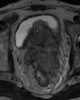

T2-hypointense prostate mass